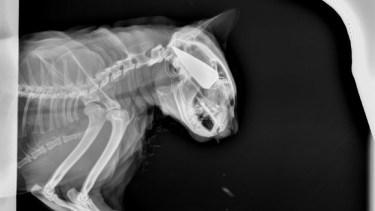

En un episodio alarmante de maltrato animal, un gato sufrió un flechazo en la cabeza en un barrio cercano al kilómetro 16 de la Ruta 1, en Viedma. El responsable, aún no identificado, fue descrito como por la dueña del animal como «un vecino».

Salem se salvó de milagro. Foto: gentileza.

La lanza que atravesó la cabeza del animal. Foto: gentileza.

A pesar de la gravedad del ataque, Salem se encuentra en recuperación y es cuidado de cerca por sus dueños y otros gatos de la casa. «Salem está bien, estamos bien», concluyó la dueña.